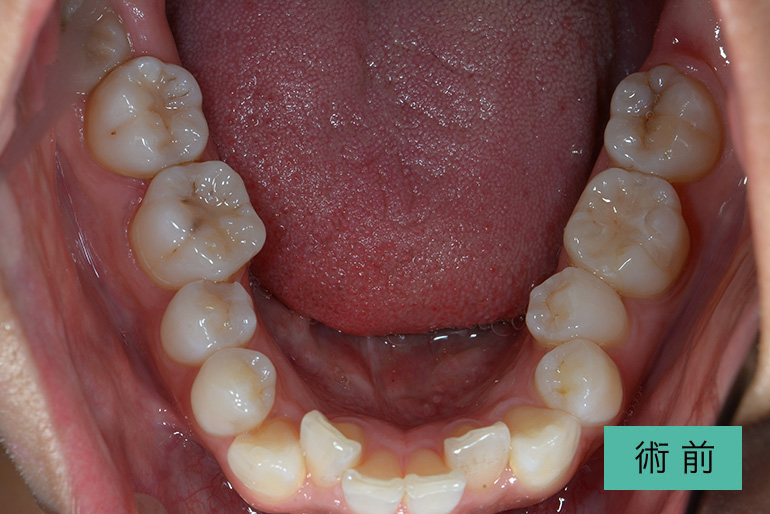

インビザライン②

| 治療内容 | 歯並びをキレイにしたい。 口腔内容積を狭くしないように、歯列を拡大し非抜歯で矯正をする。 |

|---|---|

| 治療期間・回数 | 約3年半、40回 |

| 費用(税込) | ¥880,000(マウスピース矯正) ※自由診療 |

| リスク・副作用 | 歯肉退縮、知覚過敏、後戻り |